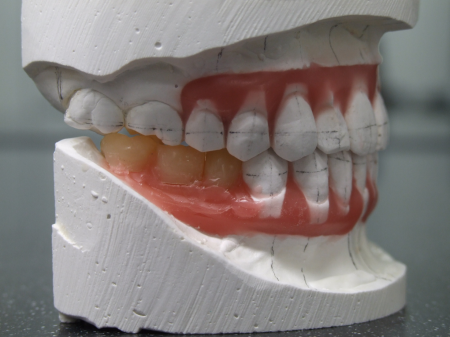

したがって右下前歯を動かさない計画のもと右下前歯の位置を基準としてそれ以外の歯を並べ直して理想的な歯並び、噛み合わせを再現した「セットアップ模型」を製作しました。

セットアップ模型:患者様の歯型をもとに作製した模型の歯の部分を切りだしてバラバラにしてから理想的な位置に並べ直して、咬合治療のゴールをシミュレーションし、確認するために用います。

このセットアップ模型を計測することでインプラントを埋入しなければならない正しい位置を知ることができます。

挺出した左上奥歯(第1大臼歯)がこの患者さまにとって最も大きな問題でした。PAというセファロ分析では、この伸び出た左上奥歯によって左右の上顎第一大臼歯結んだ咬合平面が極端に右上がりになっていました (キャント)。このままインプラントの歯をいれてしまうと顎関節症だけでなく、顔が歪んでしまうリスクもあります。しかし、全体的には咬合高径が低下した状態であったため、適切な咬合高径と咬合平面を矯正治療にてバランスよく設定するのは難しいケースでした。咬合治療の進め方としてはまず、最初に適切な咬合高径、咬合平面を決定することが重要になります。これは総入れ歯の治療と同様です(要素A)。